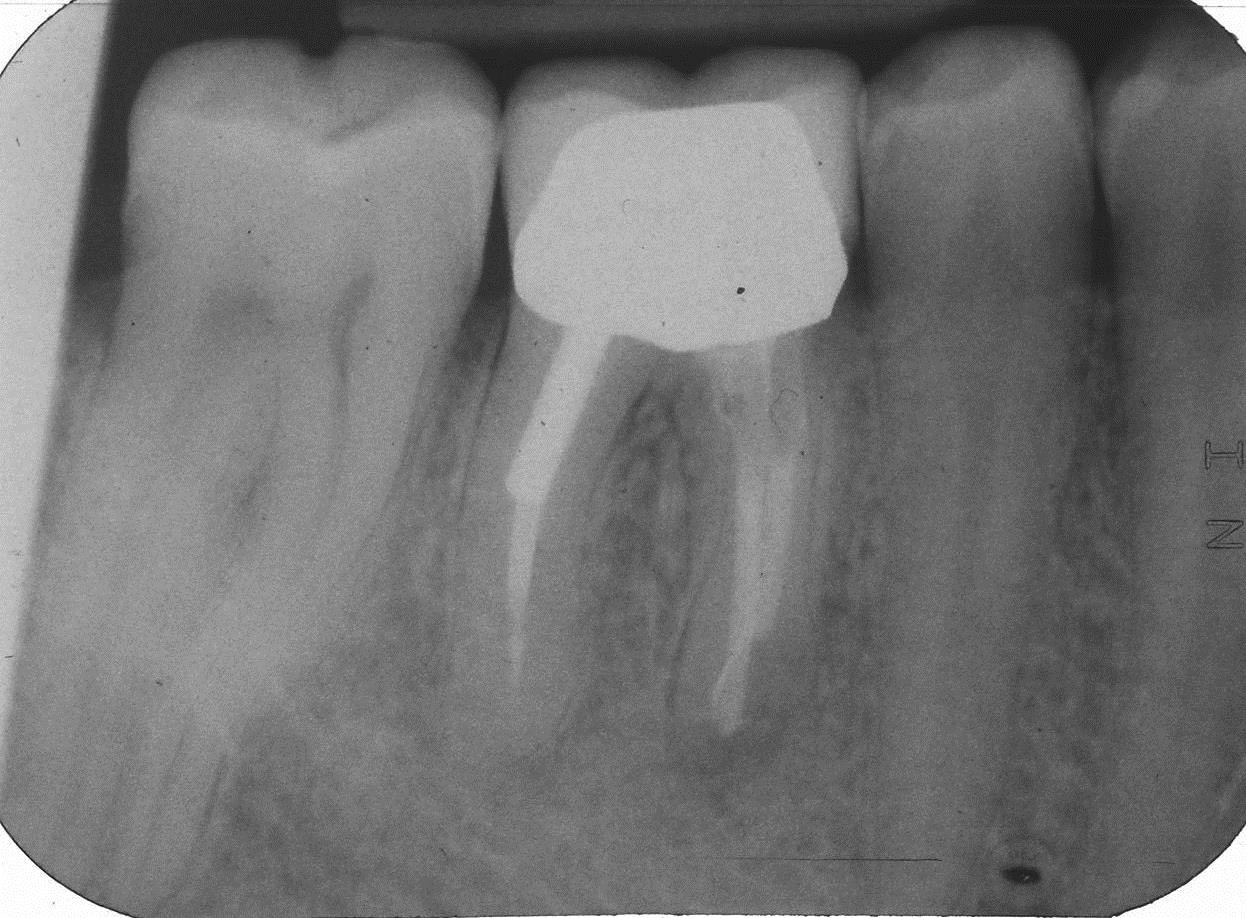

FL-5 Veröffentlicht 6. Oktober 2013 am 1246 × 918 in Teilrevision Zahn 46 – Wie würden Sie entscheiden?